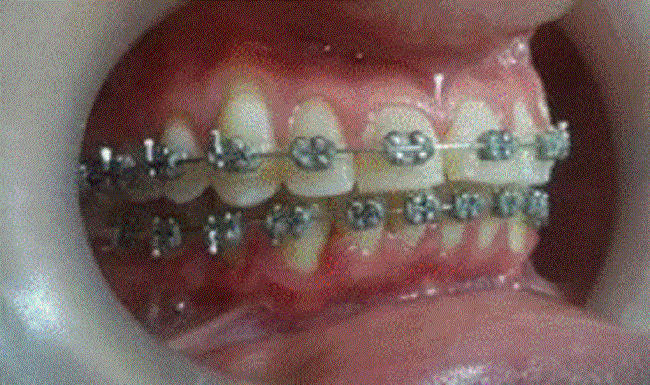

Previo a un consentimiento informado firmado y técnicas de asepsia-antisepsia, bajo anestesia local técnica mandibular derecha utilizando medio carpule de lidocaína al 2 % y lidocaína tópica gel para anestesia superficial en demás zonas quirúrgicas, se realizó exéresis de lesión de mayor tamaño y vaporización de lesiones granulomatosas generalizadas en encías con láser de diodo (GaAIAs) de 980 nm, con 2 w de potencia para lesión entre 46-47 y 1.5 w para el resto de lesiones foto 2; pulso continuó con una fibra de 300 um, logrando escisión con márgenes de 2 mm y ablación completa de las lesiones con cortes limpios, hemostasia y sin suturas. Se realizó estudio histopatológico el cual confirmó el diagnóstico de granuloma telangiectásico del embarazo. Se retiran los alambres de ortodoncia hasta después del parto, puesto que se identificaron como factor de exacerbación, también se dieron recomendaciones posquirúrgicas a la paciente que incluía enjugue con clorhexidina 0.2 % dos veces al día por una semana. No se prescribieron analgésicos, antiinflamatorios, ni antibióticos. La paciente no manifestó complicaciones foto 3.

Aspecto de área quirúrgica, durante la vaporización del epitelio de encía con láser Teniendo en cuenta el sangrado de las lesiones, el impedimento de las funciones bucales y afectación de la calidad de vida, el carácter de satelitosis y recurrencia de la patología, se decidió la eliminación quirúrgica de lesión ubicada en encía papilar entre del 46-47, estudio histopatológico y gingivoplastia, en otras zonas afectadas. Debido al riesgo de hemorragia, el número de lesiones y la extensión del procedimiento se programó el abordaje quirúrgico con láser de diodo.

Foto 2

Fuente: propia de las y los autores.